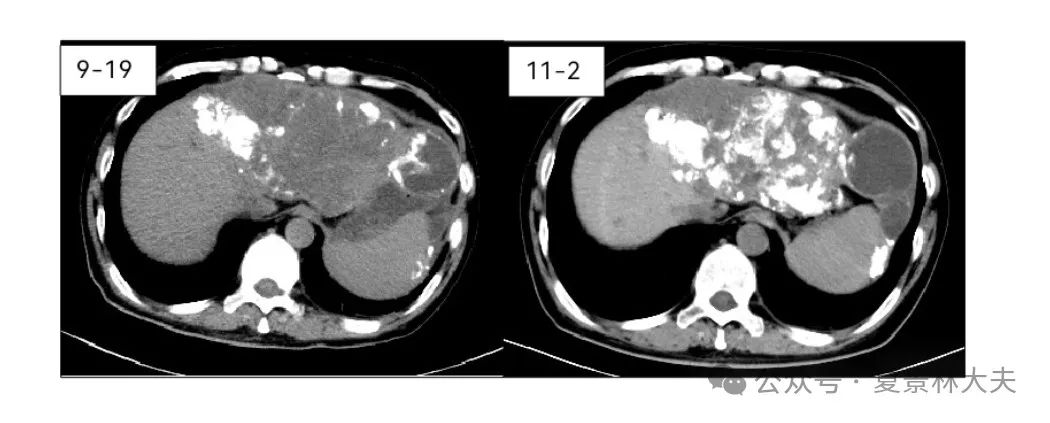

介入后,CT提示肝内碘油沉积较前明显增加(图4)。

图4.第四次介入后碘油沉积明显增多(左:介入前;右:介入后)